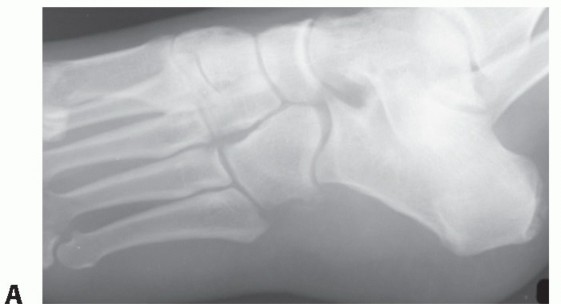

DEFINITION Freiberg infraction is an osteochondrosis of a lesser metatarsal head, most commonly involving the…